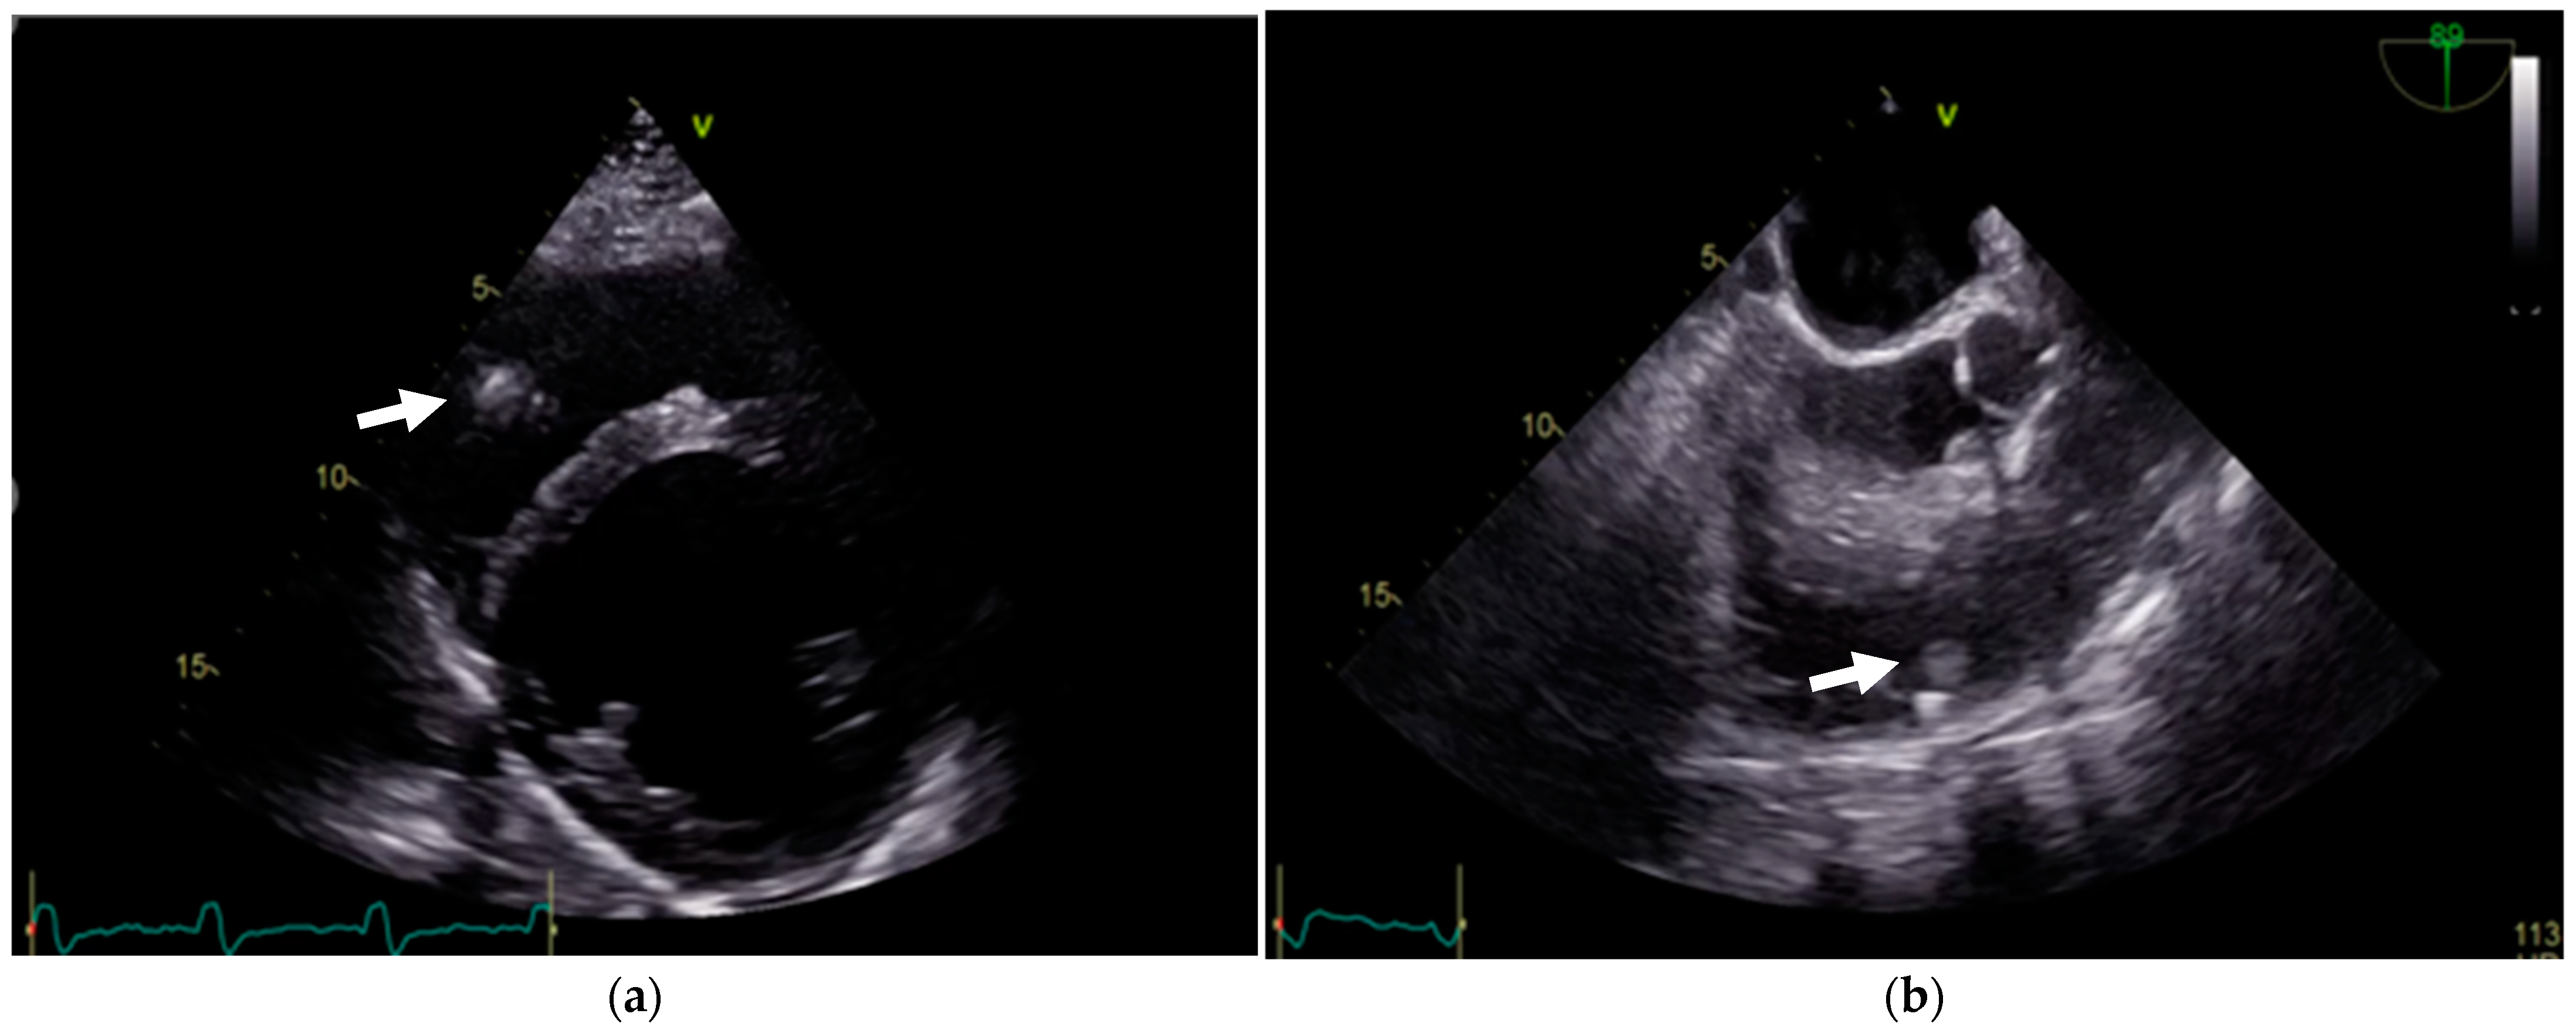

2. Case Presentation